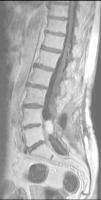

The patient underwent magnetic resonance imaging (MRI) of the low back, which revealed an intradural space-occupying lesion in the conus medullaris. It was hypervascularized and receiving its supply of blood from a rosary-like vessel,4 that extended from T10, occupying nearly the entire spinal canal to the level of L5. Spinal angiography confirmed the presence of a hypervascularized tumor irrigated by a medium-sized artery and a large, tortuous anterior spinal artery that was not amenable to embolization5,6 (Figs. 1–3).

To date, she continues to undergo clinical monitoring every 6 months and annual radiological evaluation, and is asymptomatic and the lesion has not grown (Figs. 4 and 5).